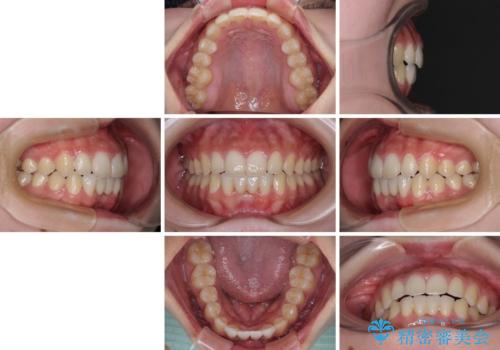

矯正治療終了後に速やかにオールセラミックブリッジを装着していくこととしました。

結婚式の予定があるとのことで、できる限り歯列を整え、挙式直前で残った乳歯を抜歯してブリッジの仮歯を装着するプランを立てたのですが、途中妊娠をされたため、麻酔をするタイミングを検討し、うまく前歯を整えることができました。